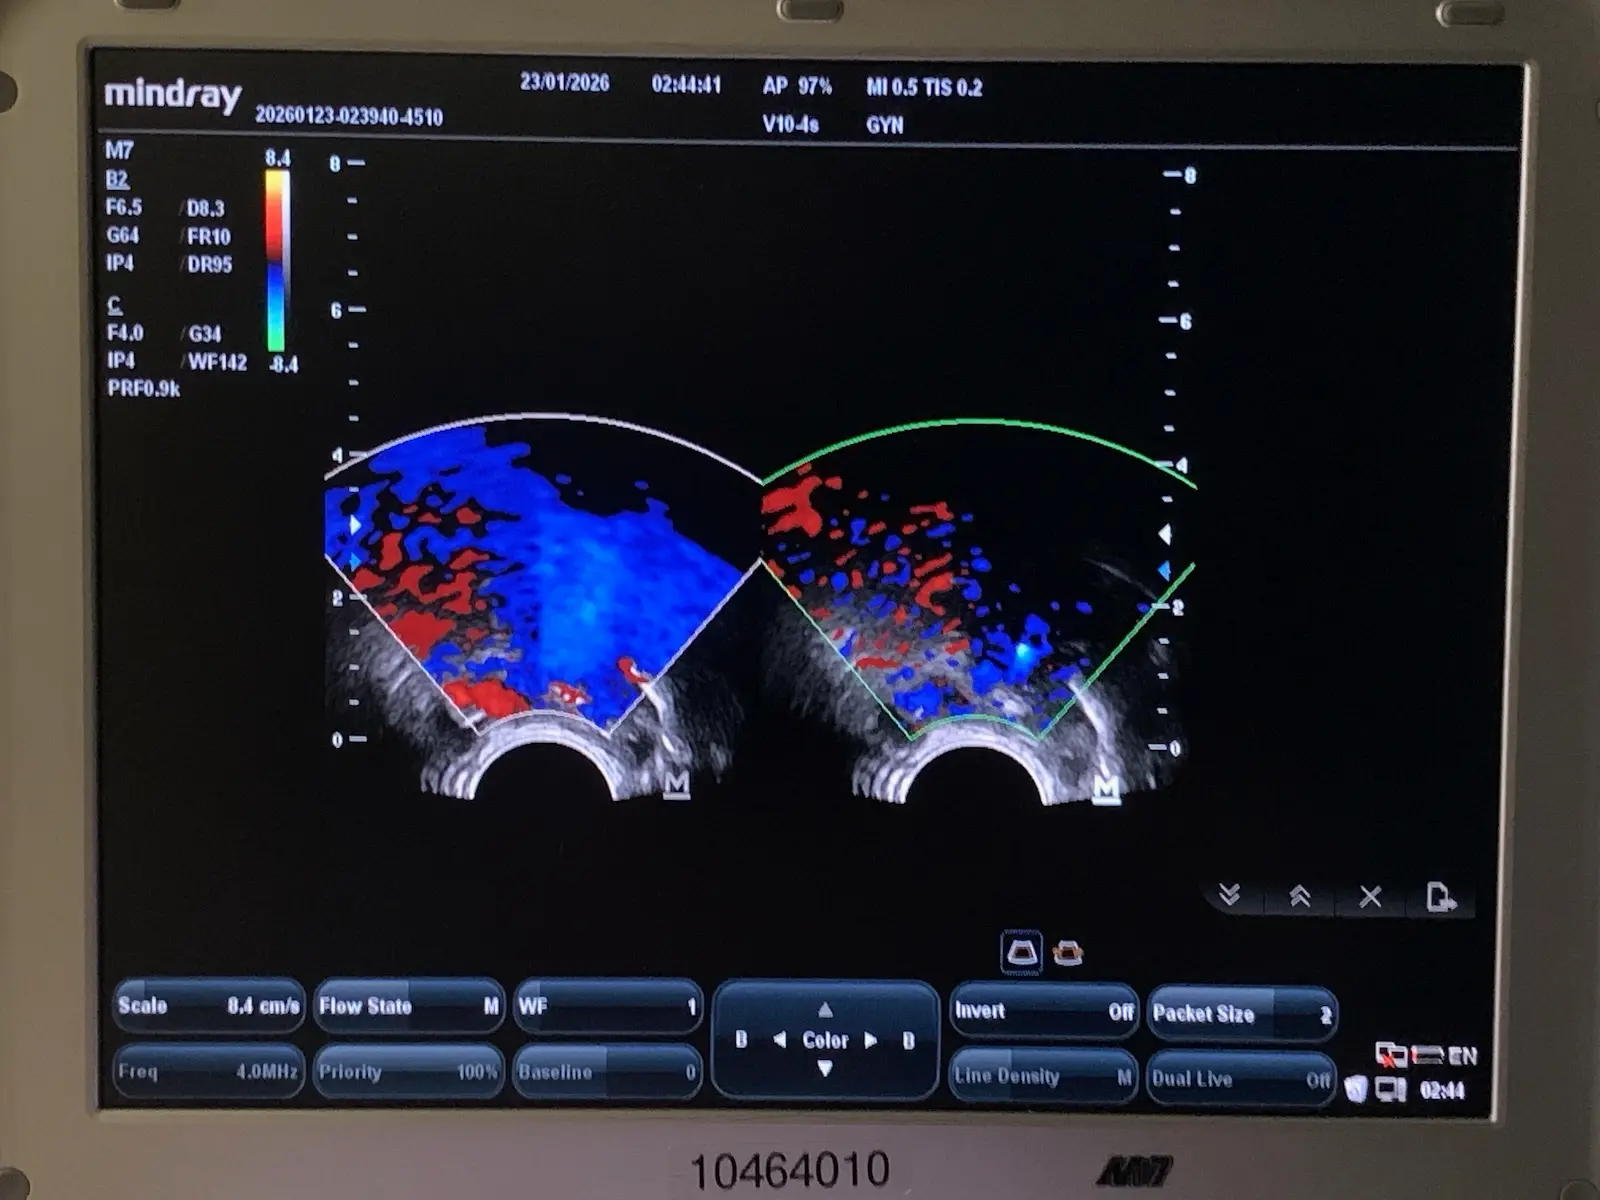

Up for sale is a genuine Mindray V10-4s curved array endocavity probe. This transducer is designed for high-resolution imaging in obstetrics, gynecology, and urology. It features a wide-band frequency range (4–10 MHz) and a small 10mm radius for patient comfort.

Source: Removed from a clinical environment. The probe was tested on a Mindray MR-M7 Ultrasound unit to confirm full functionality, image quality, and connectivity.